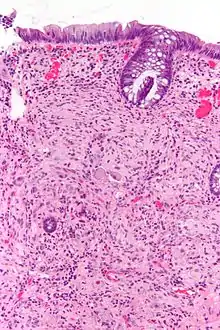

Micrograph of a ganglioneuroma with the characteristic ganglion cells. H&E stain.

Pathologically, ganglioneuromas are composed of ganglion cells, Schwann cells and fibrous tissue.[5] Ganglioneuromas are solid, firm tumours that typically are white when seen with the naked eye.